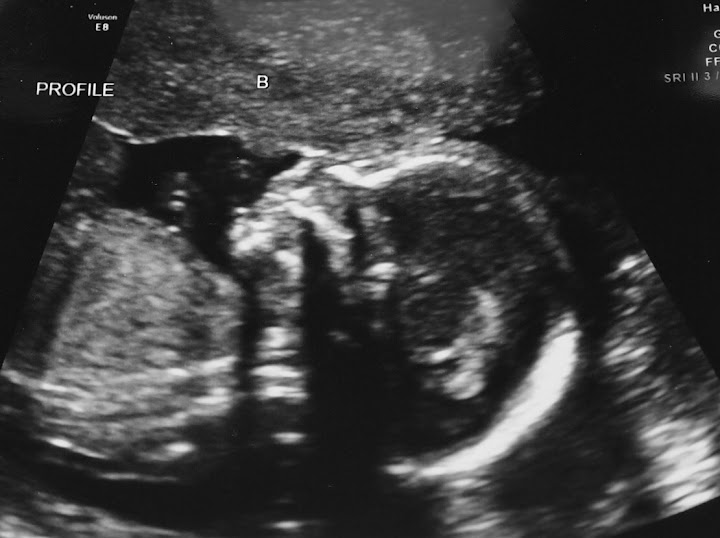

The anatomy scan went well last night (despite some logistical issues resulting in my walking about 1.5 miles through some nicer transitional areas and some not so nice areas of JErsey City AND having to get McDonalds, yuck, for dinner because our appt time was screwed up). Both babies are measuring on track (10 and 11 oz) and look good. I got to watch the whole thing which was cool since I haven't seen them since 13w. They've doubled in size since her 16w appt when they measured 6oz! However, I think they were angry because it was their second scan of the day (they had cardic echos done earlier, our peri wanted them b/c C has a mild murmur, and they're perfect!) and they totally didn't cooperate.  A still needs a scan of her left hand, and B needs the heart scans and something else I forget. It was complicated by C having some gas which obscured the screen from a few spots on her belly Stick out tongue

and here ya go (she only gave us headshots...I'll have to ask for full ones at our follow up next week I guess, and I know the tech (who is kind of bad at this) will give C full ones at her next appt in two weeks, but they're always weird angles!)

B

image